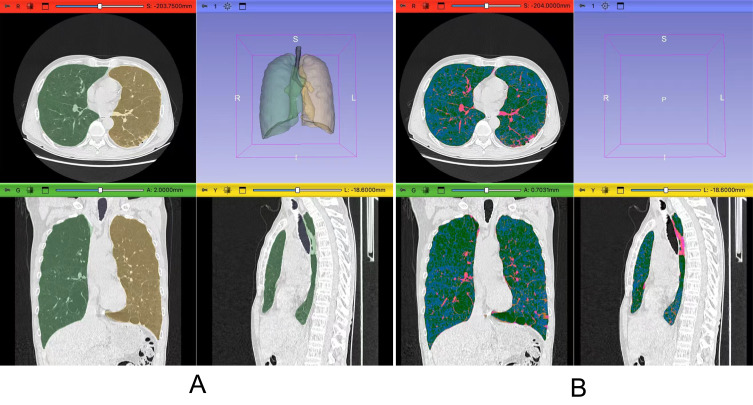

Methods: This retrospective cohort study included 392 COPD patients with no prior history of CAD between 2015 and 2020. All participants underwent HRCT for automated emphysema quantification using 3D Slicer software. Emphysema extent was quantified as the percentage of low attenuation areas (LAA%) below -950 Hounsfield units, with severe emphysema defined as LAA% >16.95%. Logistic regression and restricted cubic spline (RCS) analysis were employed to assess the relationship between emphysema index and CAD, including subgroup and interaction analyses. The ability of the emphysema index to predict CAD was evaluated using receiver operating characteristic (ROC) curves.